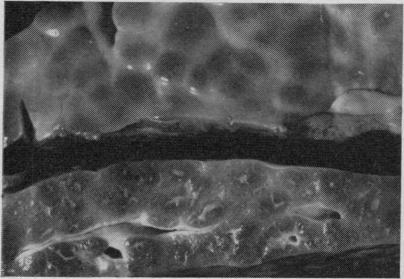

Case report. Ragwort toxicosis in a heifer.

Can Vet J. 1969 Nov;10(11):302-6.

Development of hepatic lesions in calves fed with ragwort (Senecio jacobea).